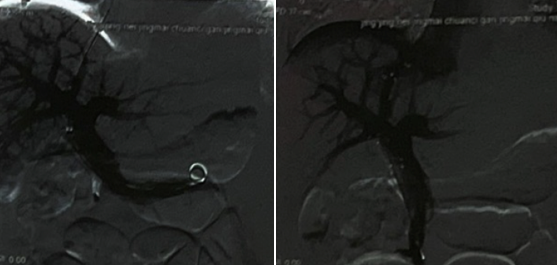

图3 TIPS

术后第9天患者再次解黑便3次,不成形,每次量约200g,当时血常规:白细胞计数1.3x109/L,红细胞计数2.73x1012/L,血红蛋白76g/L,血小板计数423x109/L。复查胃镜:食管未见曲张静脉,胃底见连片状曲张静脉团,一处见黏合剂注射后溃疡形成,表面少量渗血。动脉造影见:腹腔动脉、肠系膜上下动脉、左肾动脉、脾动脉未见活动性出血。10天后患者转至外科行脾切除术+贲门周围血管离断术,术后病理符合慢性淤血性脾肿大。